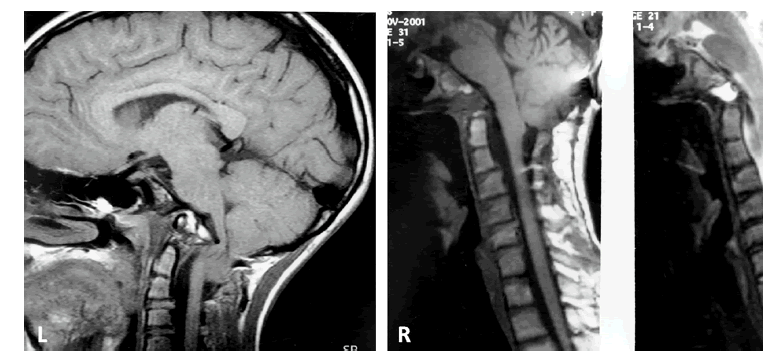

Figure 1: Case #1; Composite of preoperative (L) T1-W MRI of craniovertebral junction and postoperative (R) studies. The ventral indentation of the medulla is severe with cerebellar tonsils to C2 (L). The postoperative views (R) show decompression of medulla and cerebellar tonsillar ascent (T1-W and T2-W MRI).

Figure 2: Case #2; Composite of preoperative (L) and postoperative (R) T2-W MRI of craniocervical junction. There is a proatlas invagination into the ventral medulla (L), hindbrain herniation and cervical syringohydromyelia. The postoperative (R) image shows relief of ventral medullary compression, syrinx decompression and ascension of cerebellar tonsils.